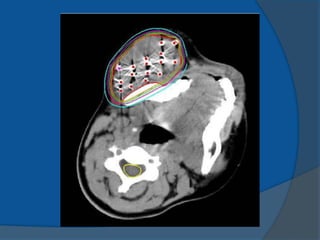

1983 Hans HenrikHolm use of transrectal ultrasound to visualize the permanent placement of I-125 seeds via needles inserted through the perineum directly into the prostate implanting I-125 seeds into cancerous prostates, under the direction of axial imaging from a rectal probe mounted on a sledge-stepper (stepping unit). 1985 Blasko and Ragde the first transperineal, ultrasound- guided approach in the United States ultrasound-guided approach resulted in increased accuracy of needle and seed placement and relatively even distribution of seeds throughout the prostate it allowed computerized treatment planning of the implant rather than the use of simple nomograms ensuring the proper number, strength, and positioning of radioactive sources.